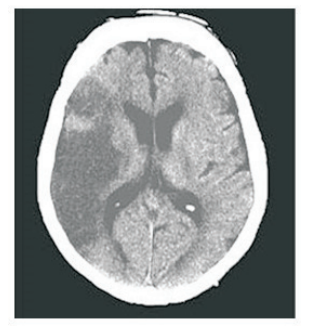

Paciente do sexo masculino, 65 anos, hipertenso e diabético, apresentou episódio súbito de hemiparesia em dimídio esquerdo. Foi solicitado Ressonância Magnética de crânio com a imagem a seguir.

enunciado 598722-1

Com relação à topografia da lesão vascular, a artéria afetada foi :